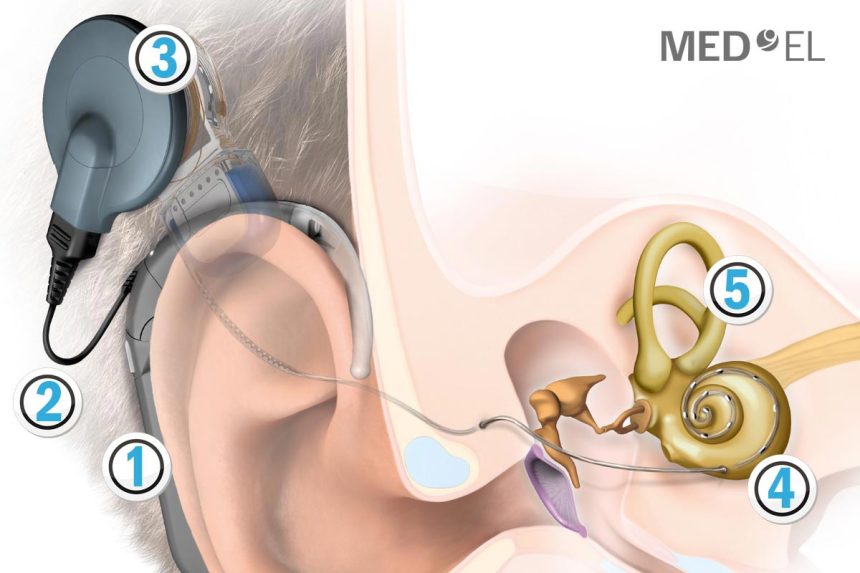

Treize (13) interventions chirurgicales de pose d’implants cochléaires ont été effectuées sur des enfants malentendants, dans le cadre d’un jumelage entre l’établissement public hospitalier EPH-Benamar Djilani (El-Oued) et le Centre hospitalo-universitaire CHU-Khelil Amrane (Bejaïa), a-t-on appris dimanche des organisateurs.

Effectuées sur des enfants âgés d’un mois à six (6) ans, ces opérations délicates, entrant dans le cadre des efforts du service d’ORL (oto-rhino-laryngologie) de l’EPH d’El-Oued, interviennent en application des recommandations du ministère de tutelle portant amélioration des prestations médico-chirurgicales, a indiqué le directeur de l’EPH d’El-Oued, Djamel Laâmouri.

Ces interventions ont été menées trois jours durant sur des enfants présentant une déficience auditive, par une équipe médicale composée de quatre (4) spécialistes en ORL et trois (3) anesthésistes-réanimateurs, assistés de paramédicaux, sous la conduite du Pr. Mustapha Sellami, chef de service ORL au CHU de Bejaia. Des moyens et équipements médicaux modernes ont été mobilisés pour la réussite de cette action qui sera renouvelée pour profiter à un plus grand nombre de malades et leur épargner les déplacements vers les CHU dans d’autres wilayas, a souligné M.Laâmouri. Le programme de ce jumelage a comporté, en parallèle, une session de formation et d’échange d’expériences médicales en direction des équipes médicales et paramédicales locales, encadrée par le Pr. Sellami, sur des thèmes en rapport avec la spécialité ORL.

Jumelage inter-hôpitaux : Treize poses d’implants cochléaire effectuées à El-Oued